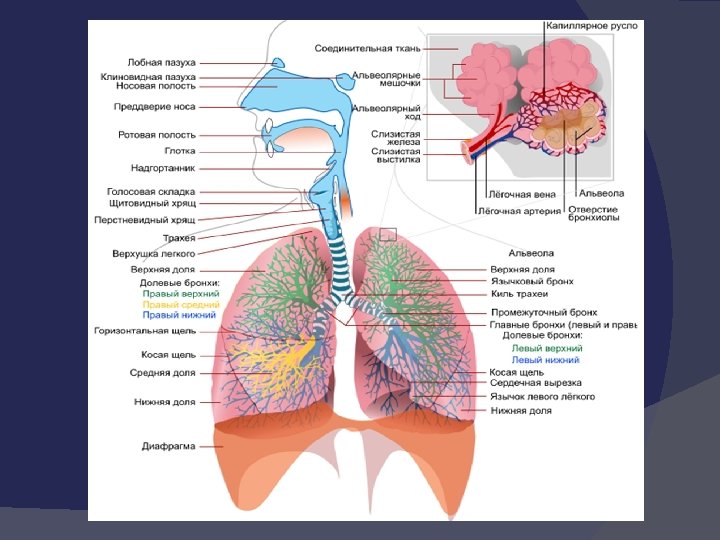

ПНЕВМОНИЯ Острое инфекционное заболевание, преимущественно бактериальной этиологии, характеризующееся очаговым (локальным)поражением респираторных отделов легких, наличием альвеолярной экссудации и выражеными в различной степени лихорадкой и интоксикацией.

Клиническая картина Интоксикационый синдром Бронхитический синдром Синдром поражения легочной паренхимы